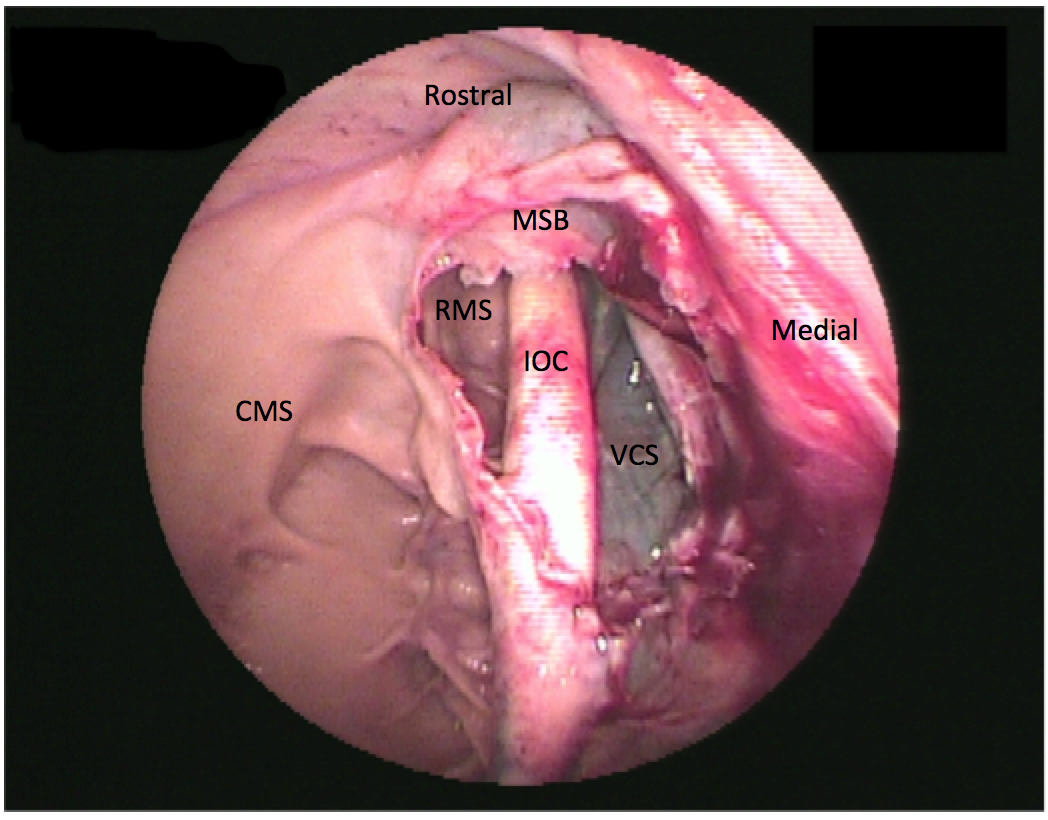

The rostral maxillary sinus and the ventral conchal sinus are frequent sites of infection caused by apical dental infection or inspissated exudate, respectively. However, these sinuses are not directly accessible from trephine holes into the conchofrontal or caudal maxillary sinuses (Figure 1). The rostral maxillary sinus can be examined independently through a rostrally placed maxillary bone trephination. However, this is generally not recommended in young horses to avoid iatrogenic damage to the reserve crowns of the ninth and 10th maxillary teeth. The ventral conchal sinus and rostral maxillary sinus can both be evaluated through a portal into the conchofrontal or caudal maxillary sinuses after fenestration of the cartilaginous maxillary septal bulla (formerly termed ventral conchal bulla). The maxillary septal bulla is desensitized with topical local anesthetics and fenestrated with endoscopic guidance using a Ferris-Smith arthroscopic rongeur, crocodile forceps, or diode laser via the same portal as the endoscope (Figure 2). If fenestration of the bulla causes bleeding that obscures observation, sinoscopy should be repeated after 24 to 48 hours. Lavage of all compartments is possible after fenestrating the bulla.4

Figure 2.